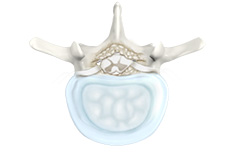

Herniated Disc (Lumbar)

Herniated disc is a condition in which the outer fibers (annulus) of the intervertebral disc are damaged causing the soft inner material of the nucleus pulposus to rupture out of its space. A herniated disc, common in the lower back (lumbar spine) occurs when there is a tear in the outer lining of the disc (annulus fibrosus). This causes the inner jelly-like material (nucleus pulposus) to leak out and place pressure on the adjacent spinal nerve root. It is the most common cause of lower back pain and pain that radiates down the leg (radiculopathy).

Lumbar Herniated Disc

A herniated disc is a condition in which the outer fibers (annulus) of the intervertebral disc are damaged, causing the soft inner material of the nucleus pulposus to rupture out of its space. It is the most common cause of lower back pain and pain that radiates down the leg (radiculopathy).

Lumbar Disc Herniation

Lumbar disc herniation is the most common cause of lower back pain and leg pain (sciatica). Aging, injury or trauma may cause the annulus fibrosus to tear, resulting in protrusion of the nucleus pulposus. This may compress the spinal nerves and/or spinal canal.

Disc Herniation

Disc herniation is a condition where the central nucleus pushes through the outer edge of the disc, causing a bulge that compresses the spinal nerves.